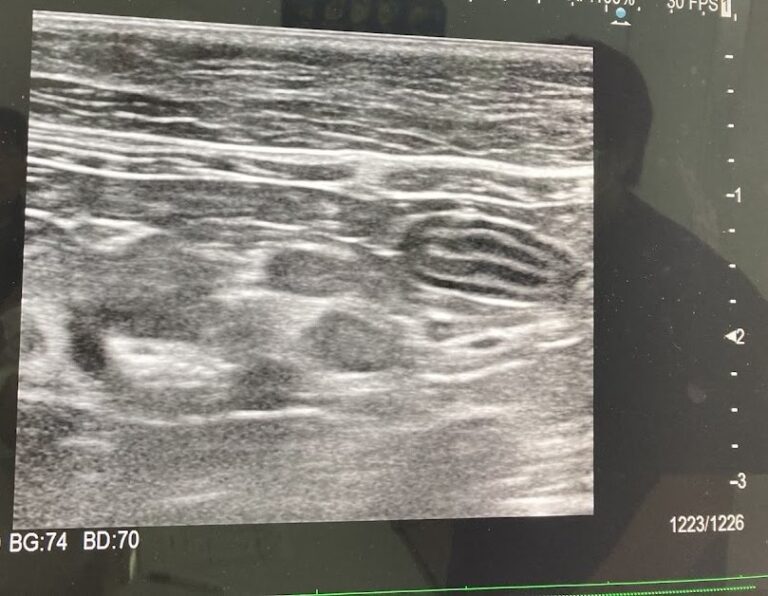

そこで、エコー検査をしてもらい、「小腸の5層構造の乱れ」「肝臓に異常があるかも」と言われました。

さらに、エコーで診てもらい、肝臓がボコボコしていること、心臓肥大とまでいかないけれど異常があるかもしれないと言われて、改めて設備の整った病院の診察を勧められました。

そうなったら、第二手段となるのはエコーやレントゲンです。

確定はできなくても、ガンを見つけられたかもしれない。

そこに、もっとかけておけばよかったと、年末から4月の間に、もう一度でもエコー・レントゲン検査をしてもらっていたら、そこで推測でいいから治療をはじめていたら、胸水がたまるまで悪化しなかったもしれません。